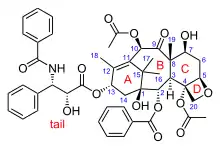

The nomenclature for paclitaxel is structured on a tetracyclic 17-atom skeleton. There are a total of 11 stereocenters. The active stereoisomer is (−)-paclitaxel (shown here).

As of 2006, five additional research groups had reported successful total syntheses of paclitaxel: Wender et al. in 1997, and Kuwajima et al. and Mukaiyama et al. in 1998 with further linear syntheses, and Danishefsky et al. in 1996 and Takahashi et al. in 2006 with further convergent syntheses. As of that date, all strategies had aimed to prepare a 10-deacetylbaccatin-type core containing the ABCD ring system, followed generally by last stage addition of the "tail" to the 13-hydroxyl group.[45]